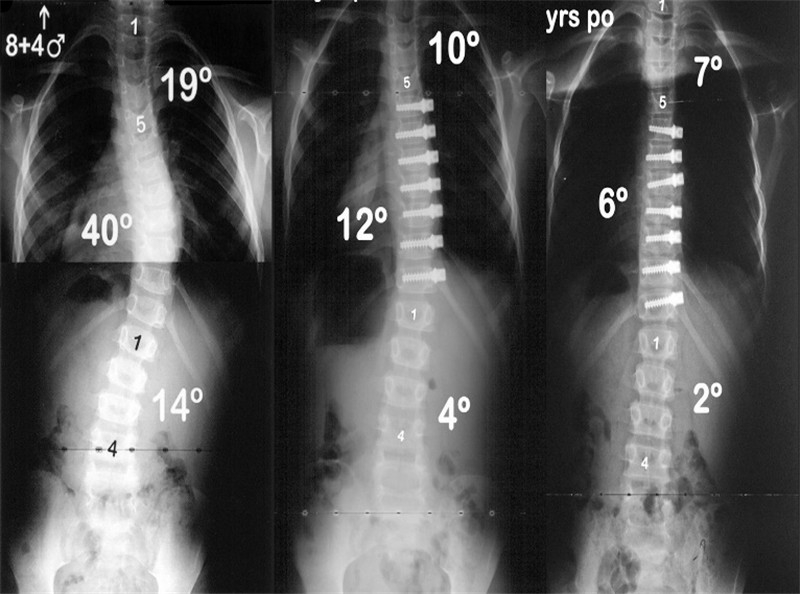

图3 6岁EOIS患儿,术前冠状面全脊柱正位X片(左),采用双生长棒技术,两端固定,顶椎撑开,术后6月复查正位X片(右)